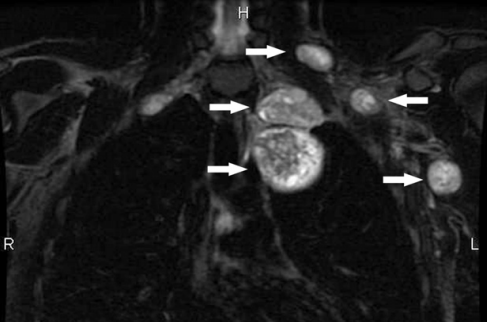

2型神经纤维瘤病是以神经系统中非癌性肿瘤的生长为特征的疾病。与2型神经纤维瘤病相关的较常见的肿瘤称为前庭神经鞘瘤或听神经瘤。这些生长沿着将信息从内耳传递到大脑(听神经)的神经发育。在这种情况下,通常还会发现发生在其他神经上的肿瘤。

2型神经纤维瘤病的体征和症状通常出现在青春期或二十多岁,尽管它们可以在任何年龄开始。前庭神经鞘瘤常见的早期症状是听力下降,耳鸣(耳鸣)和平衡问题。在大多数情况下,这些肿瘤会在30岁时出现在两只耳朵上。如果肿瘤在神经系统的其他部位发展,则其体征和症状会根据其位置而异。肿瘤生长的并发症可能包括视力变化,手臂或腿部麻木或无力以及脑部积水。一些患有2型神经纤维瘤病的人也会在一只或两只眼睛上出现晶状体混浊(白内障),通常是在儿童时期开始的。